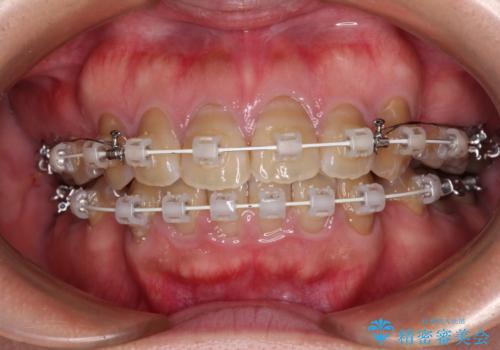

- 審美装置

- 2年6ヶ月

上下前歯が著しく前突している状態であったので、上下左右の第1小臼歯4本を抜歯し、ワイヤー装置にて矯正治療を行うこととしました。